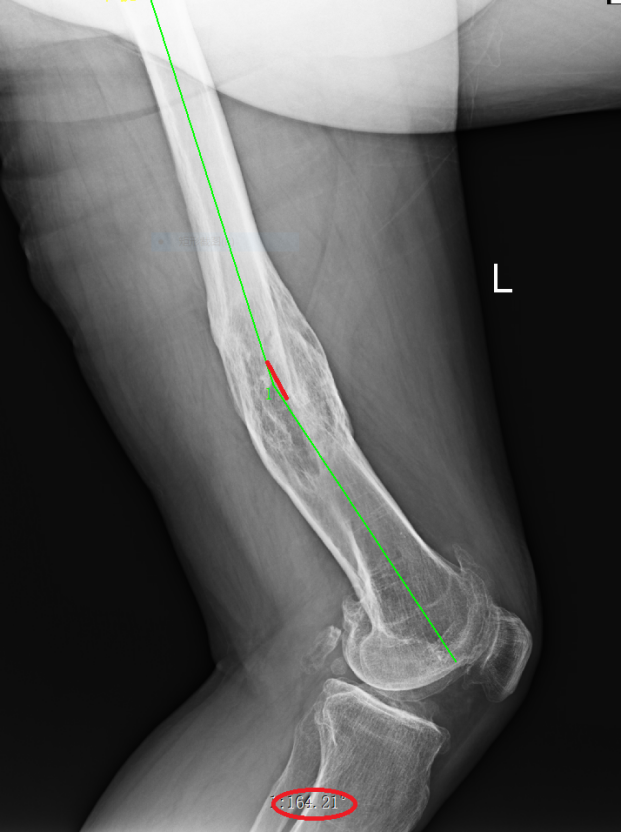

术前X线片(向后成角17°)

武明鑫教授为其仔细体格检查,发现患者左大腿中下段外侧可见一处12cm陈旧性切口疤痕,膝关节内翻畸形,大腿中下段向外成角,膝关节内外侧局部压痛,内侧尤为明显,未触及骨擦感及反常活动,肌力Ⅳ级,肌张力降低,左下肢较右下肢缩短约5.0厘米。拍X射线片检查示:1.左股骨中下段骨质膨隆并股骨弯曲,考虑是左股骨中下段骨折畸形愈合。2.左侧膝关节退行性变。